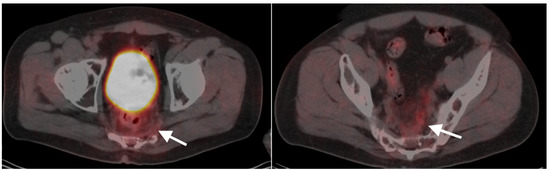

10. Anal Carcinoma